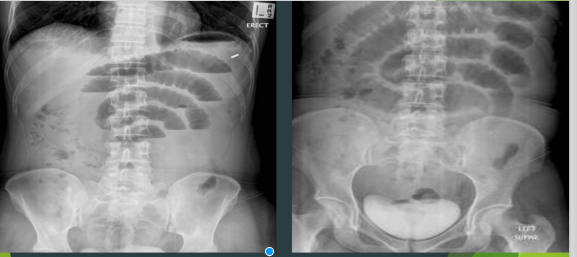

SMALL BOWEL OBSTRUCTION

TWO PATIENTS WITH